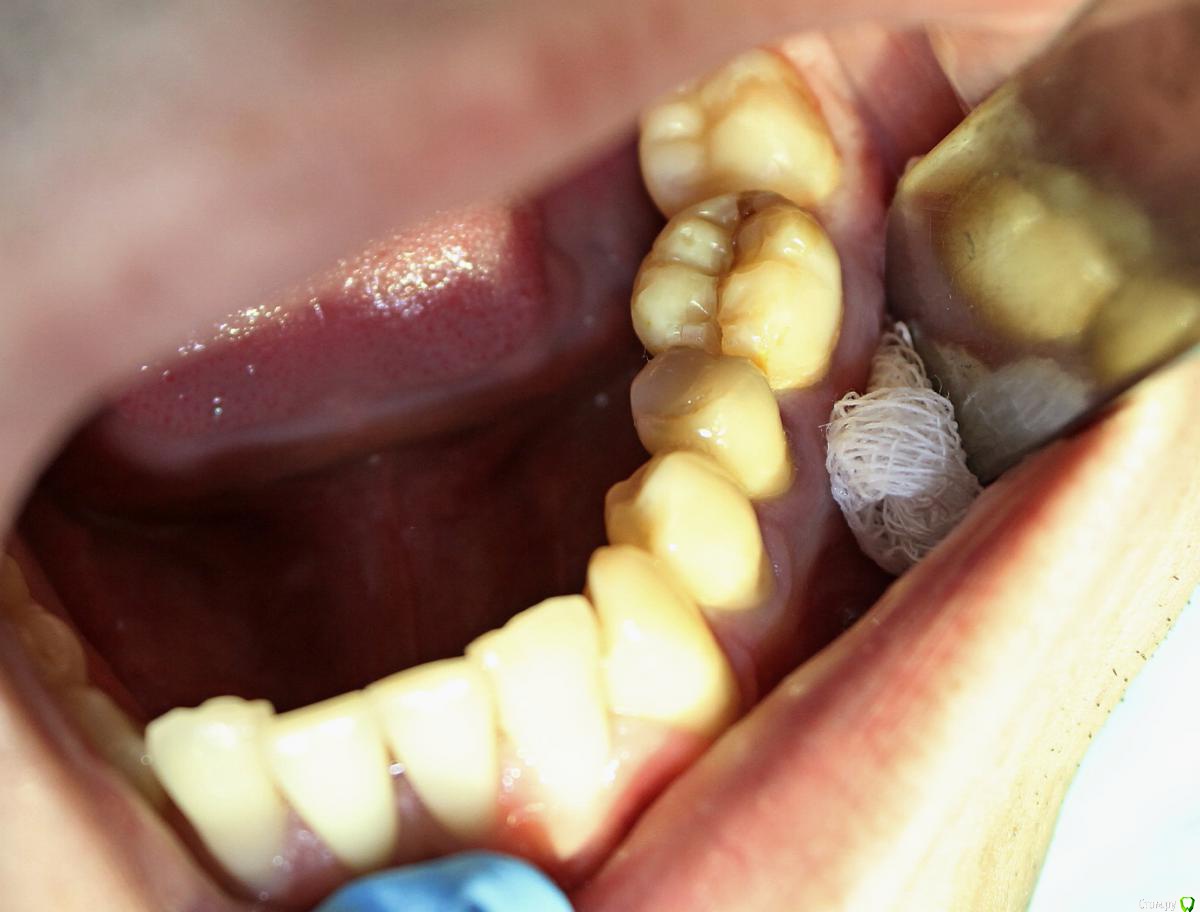

ARislanV Опубликовано 28 мая, 2015 Поделиться Опубликовано 28 мая, 2015 Приветствую всех, Здравствуйте, Начинаем!Пол года назад лечил 36Pt зуб, коронковая часть разрушена на 70 %, восстановил все композитом с перекрытием бугров.Сейчас зуб треснул, по словам удалявшего хирурга трещина до бифуркации. Почему он раскололся? Ведь что интересно, трещина прошла не по краю зуб/пломба ( в самом слабом месте), а посередине пломбы т.е. пломба разорвалась по палам. А какая сила должна была быть, что бы разорвать пломбу по полам?) И следующий вопрос, что делать и как делать, чтобы такого не было? ( потому что мне было очень не приятно видеть такое со своей работой) Ссылка на комментарий

ARislanV Опубликовано 28 мая, 2015 Автор Поделиться Опубликовано 28 мая, 2015 Я такие зубы когда пац не хочет протезироват, делаю запис в карте что рекомендовано тота тота с последствиями ознакомлен и т.п. Половина зуба заливаю жидким композитом а потом пакуемым вост сверху но стенки зуба укоротив по высоте и это укорочение компенсирую пакуемым. Типа как внутри полости пломба с переходом на края стенок. Пломба ввиде грибка. Палюбому ел кашу))Мой зуб был восстановлен именно таким способом, как вы описываете( в виде гриба)Но какова должна была быть сила, что бы разорвать пломбу пополам? Ссылка на комментарий